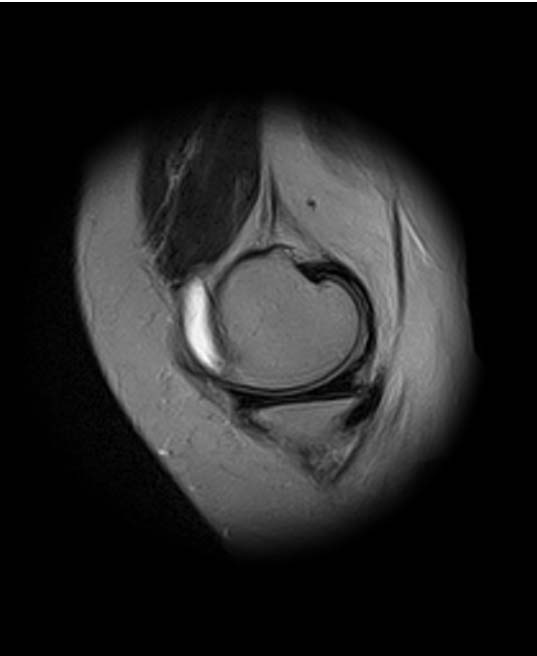

добрый день! Не очень понятен принцип, по которому отбирались снимки МРТ. Большинство из них не показательны. Вижу пока только повреждение хряща на феморопателлярной поверхности. Хлтелось бы посмотреть диск целиком

На снимках повреждений наружного мениска не вижу и кисты мениска не вижу. Есть повреждение хряща на передней поверхности внутреннего мыщелка бедра. Вполне может оказаться, что повреждение лоскутное. А какая консервативная терапия проводилась?